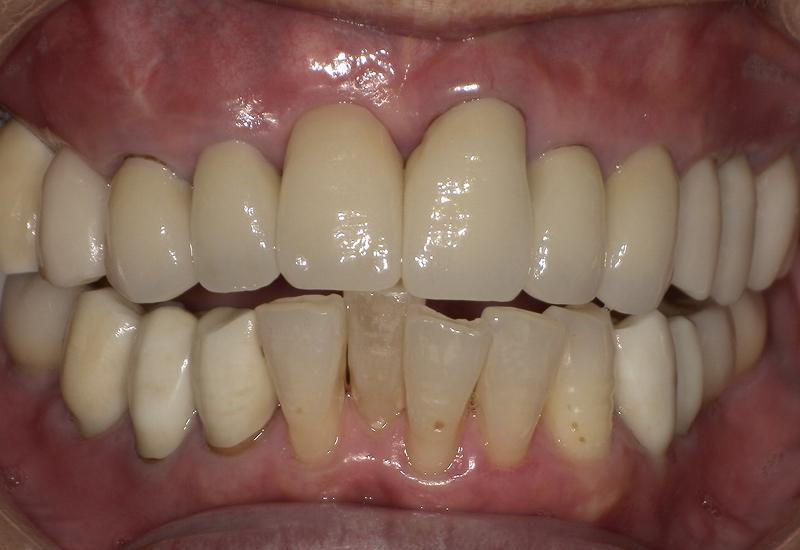

症例① シェイプメモリーアライナーによる下顎の前歯の矯正

治療期間 7ヶ月

治療時の年齢/性別 68歳 / 女性

かかった治療費 440,000円

治療方法 シェイプメモリーアライナー

注意点・詳細

• 根管治療をしてある歯はなるべく動かさない

• 下の前歯の歯の形を少しだけ小さく整えた